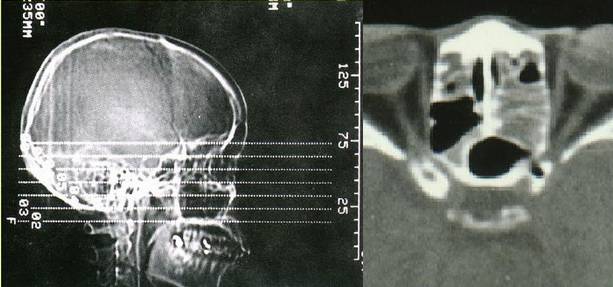

- 副鼻窦X线检查,CT(冠状位、轴位)检查已常规应用。

正常鼻窦CT

鼻窦炎轴位CT

鼻窦炎冠状CT